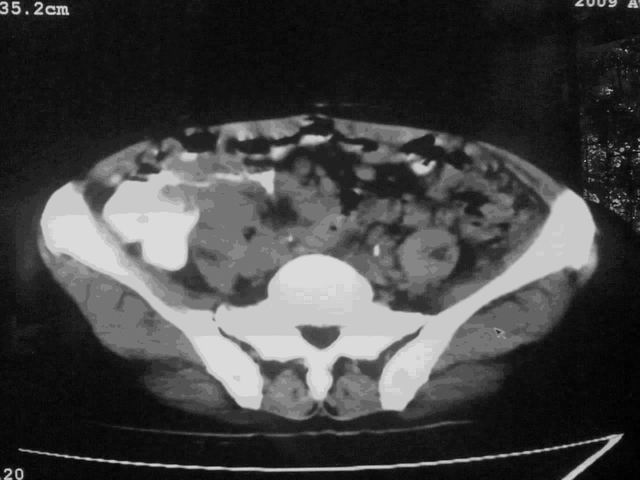

好象是横结肠占位肝转移,胰头占位?【伙计,您的片也真够意思】

伪影太多,考虑降结肠癌伴肝转移,胆囊炎

伪影太多,考虑升结肠癌伴肝转移,胆囊炎

考虑升结肠癌伴肝转移;胆囊炎。

结肠占位并肝及腹膜后淋巴结转移。